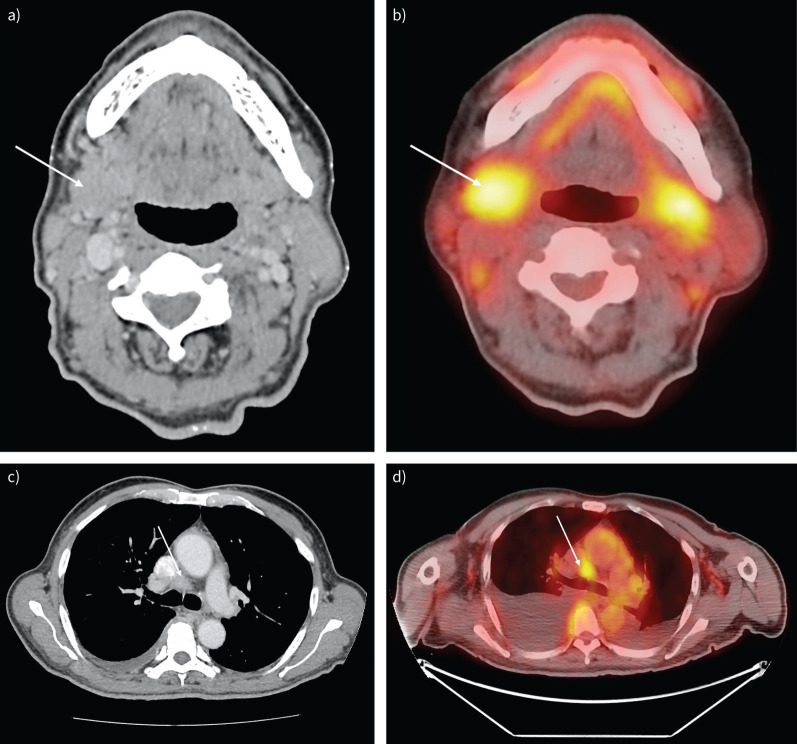

A 69-year-old man with generalised lymphadenopathy, glandular swelling and pleural effusion.

Patients with multisystemic presentation including respiratory symptoms and generalised lymphadenopathy should alert the clinician to this potential diagnosis https://bit.ly/4eJ0PHT.